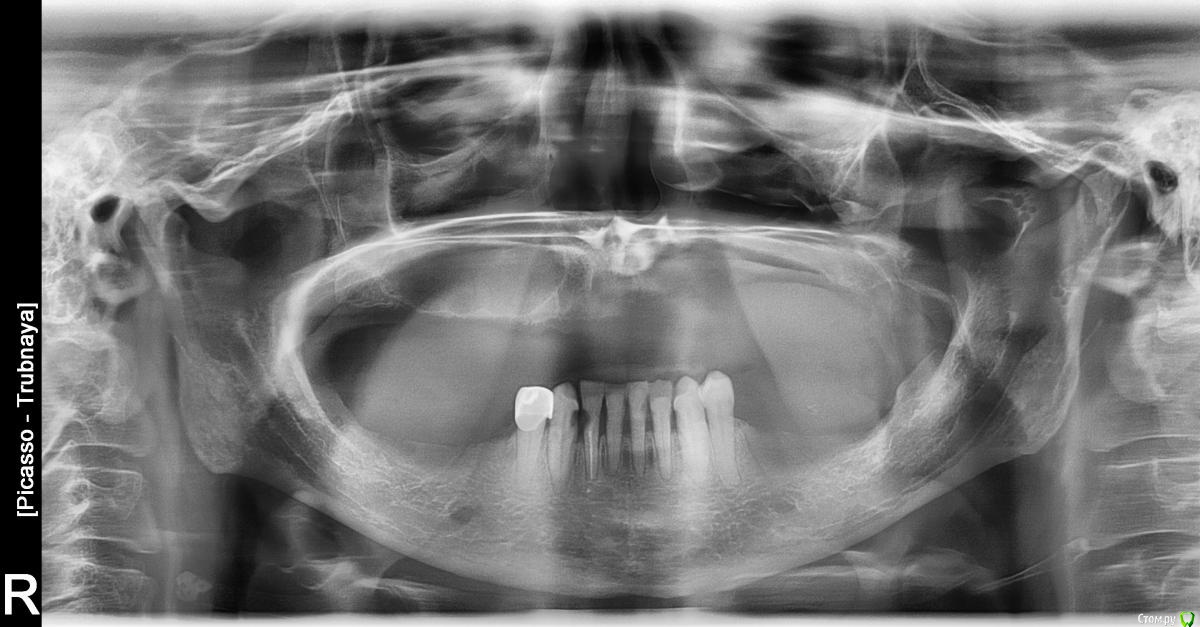

Хронический остеомиелит верхней челюсти, нижнемедиальной стенки.

Теорию найти в интернете можно, а вот на практике....кто имеет опыт. Можно ли сделать альвеэктомию в области 23 зуба.Когда удалила этот зуб, то была такая рекомендация, но никто не взялся. И вот прошло 5 лет, а в этой области неспокойно,  в области дна носа, т.е. между пазухой и полостью носа. Я чувствую там инородное тело, повышенное количество слизи слева, закладывает и т.д.